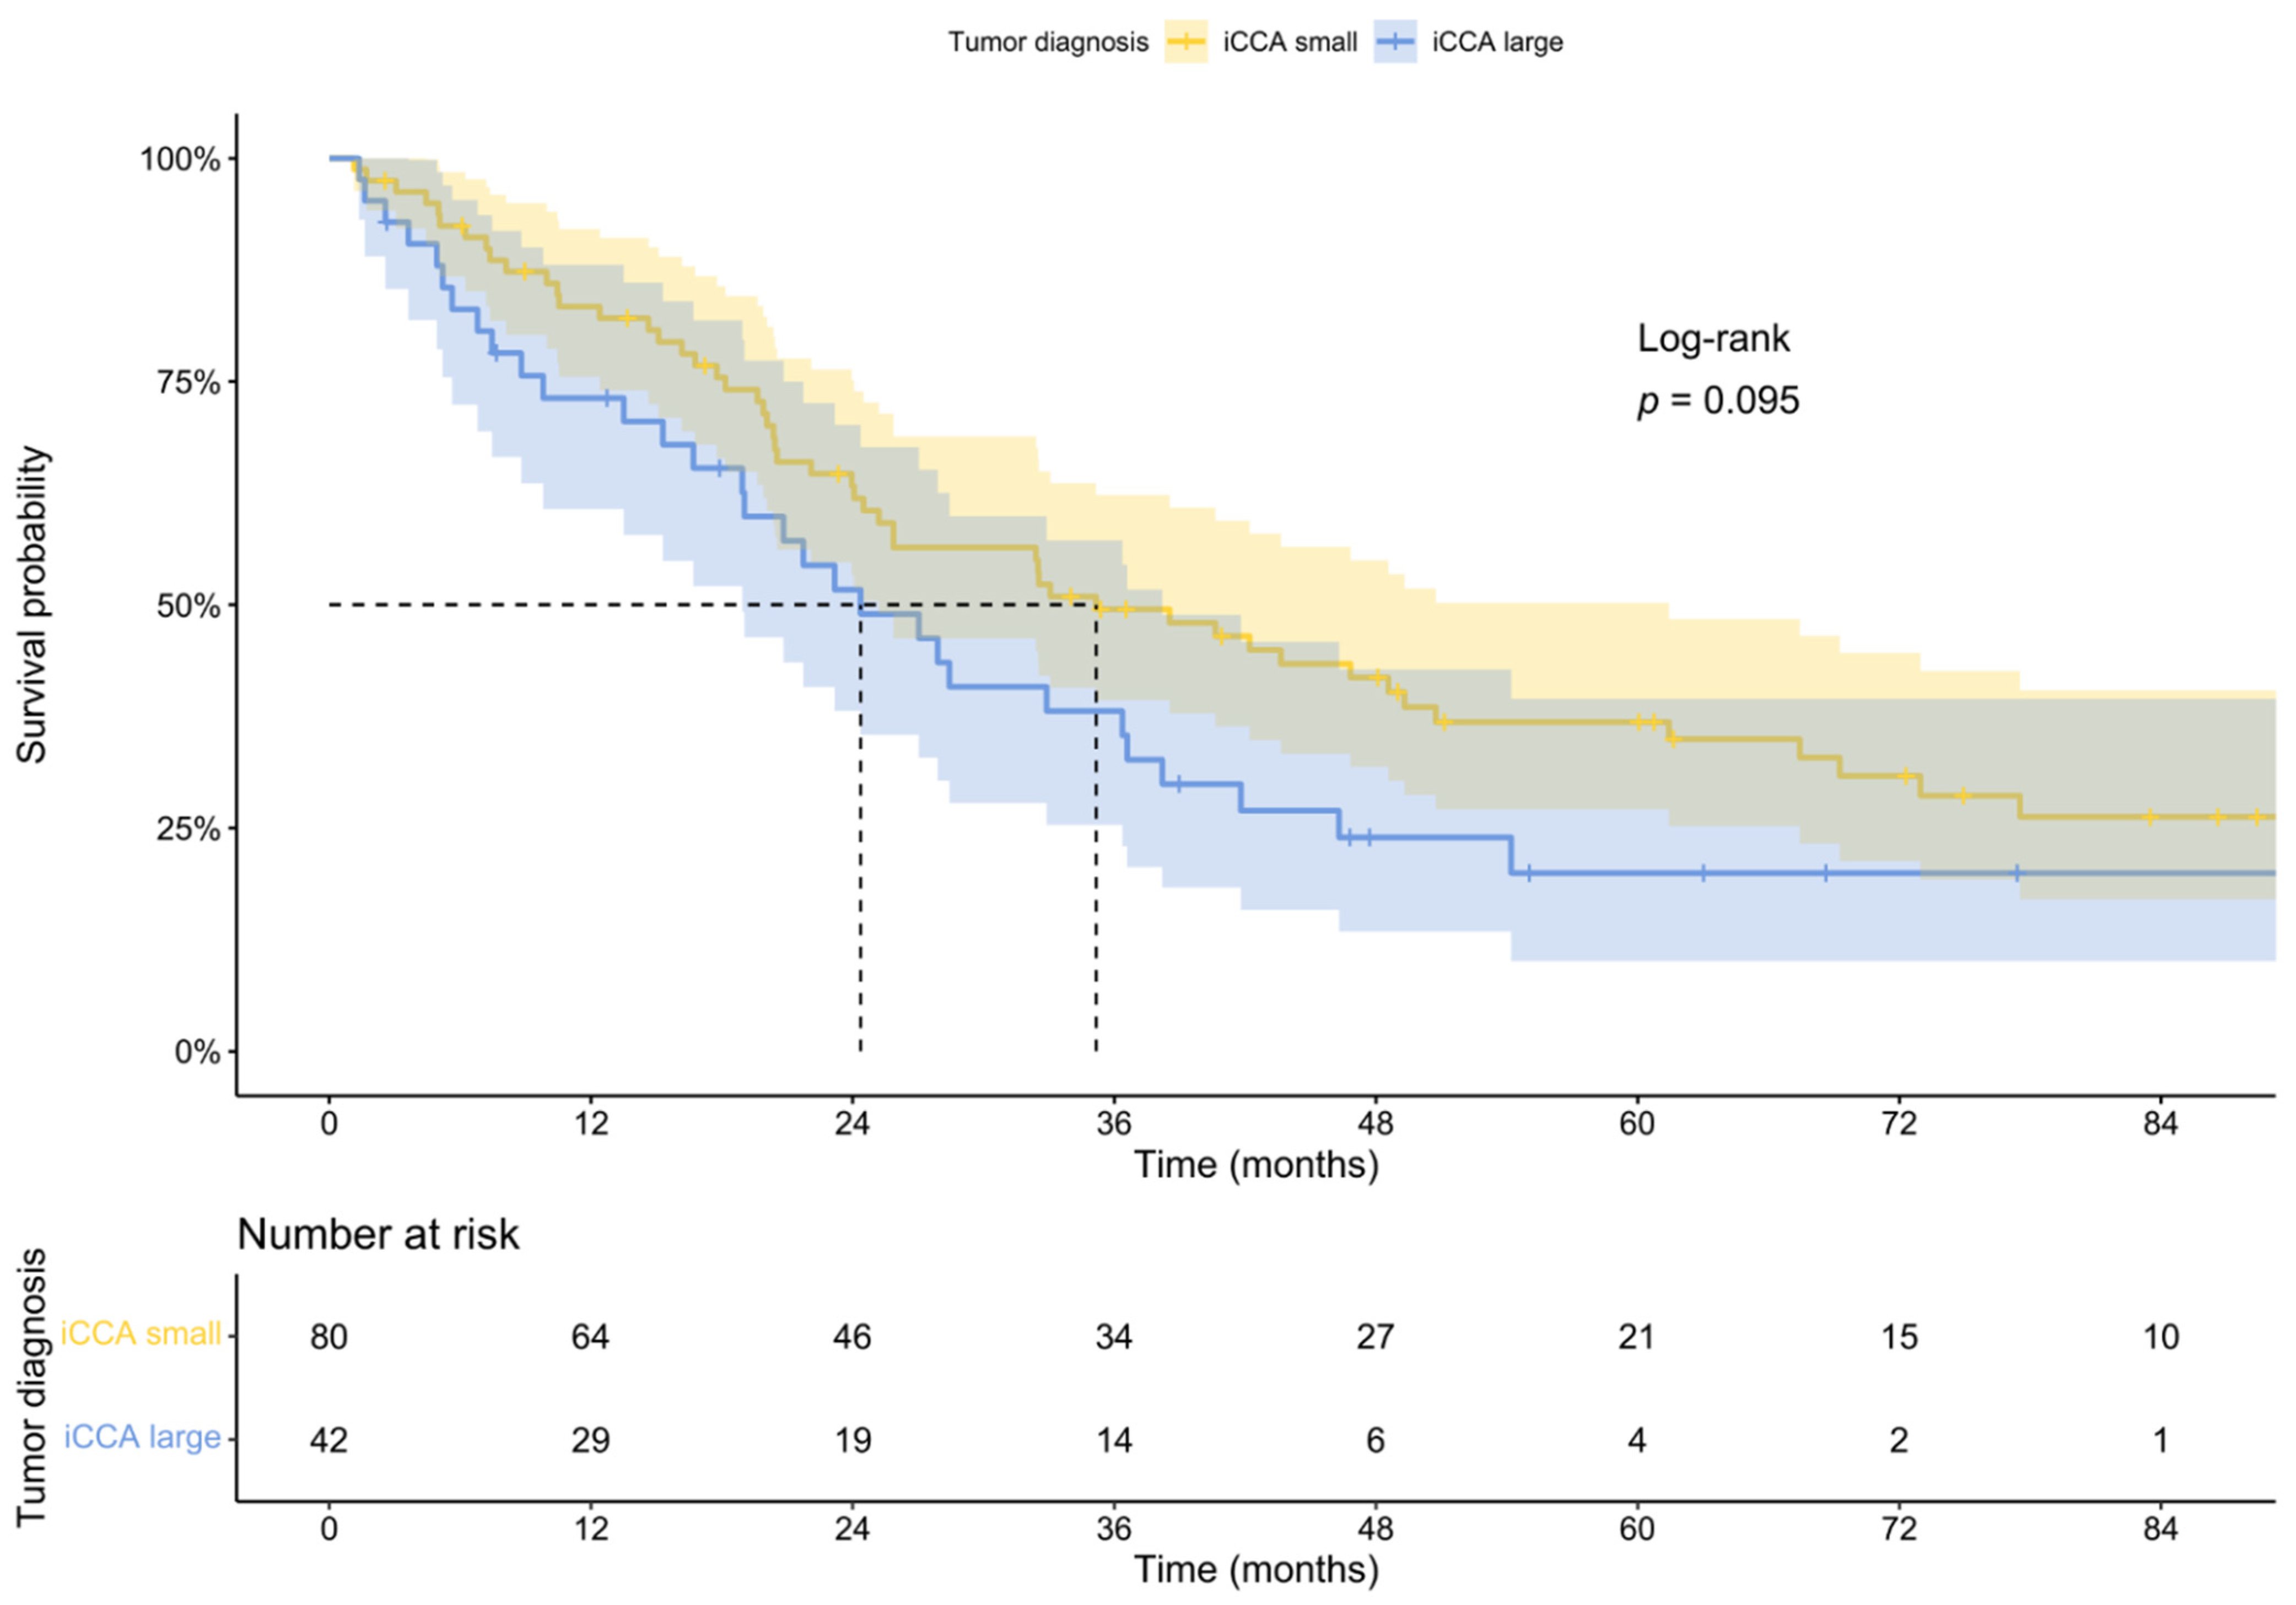

2.4. Patient Survival

| Recurrence [%] | 51 | 60 | ||||||

| Months to recurrence [mean ± sd] | 15.66 ± 23.51 | 11.24 ± 11.05 | ||||||